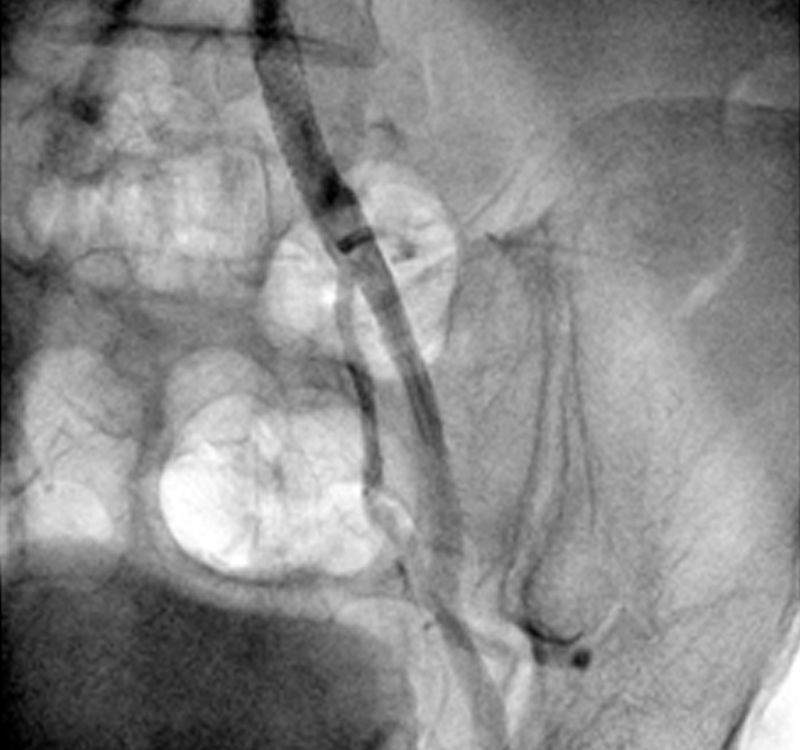

A 56 year old gentleman presented with pain in left leg while walking. He was diabetic and hypertensive. His left lower limb pulse was not palpable. Angiography of his lower limb vessel from radial route was done which showed minor plaque in right side of leg while there was significant blockage (80-90%) in the main vessel of the left leg.

Most of the cardiologist will open the critical blockage in the left leg by inserting catheter from the right leg. Doing these types of cases from radial artery (vessel of hand) is always challenging and one has to have clear idea of approach and familiarity with the hard wire used for performing these types of procedure without any complication.

Critical blockage of left leg was successfully dilated with the balloon and subsequently stent was placed without any complication. Cannula from the arm was immediately removed after the procedure and patient could walk immediately after the procedure. If we do such types of cases by femoral route, patient has to be one bed at least for next 10-12 hours and patient even not allowed to fold the legs for at least 10-12 hours. Patient was discharged successfully next day morning.